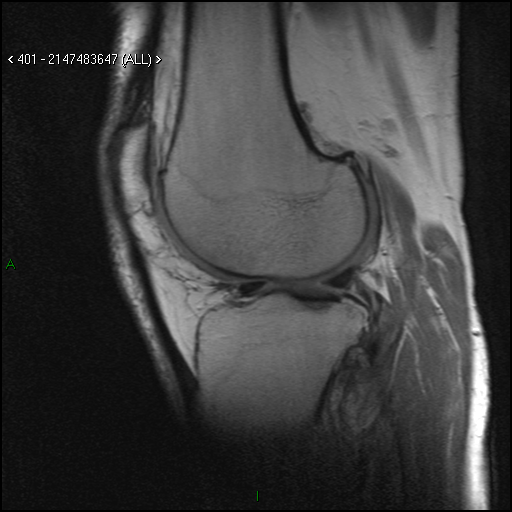

An example of an MRI examination performed at the Carolina Medical Center in Warsaw and another medical facility:

Images of the knee joint – damage to the meniscus and cartilage (MRI)

Fig. 2 – examination performed at another medical facility